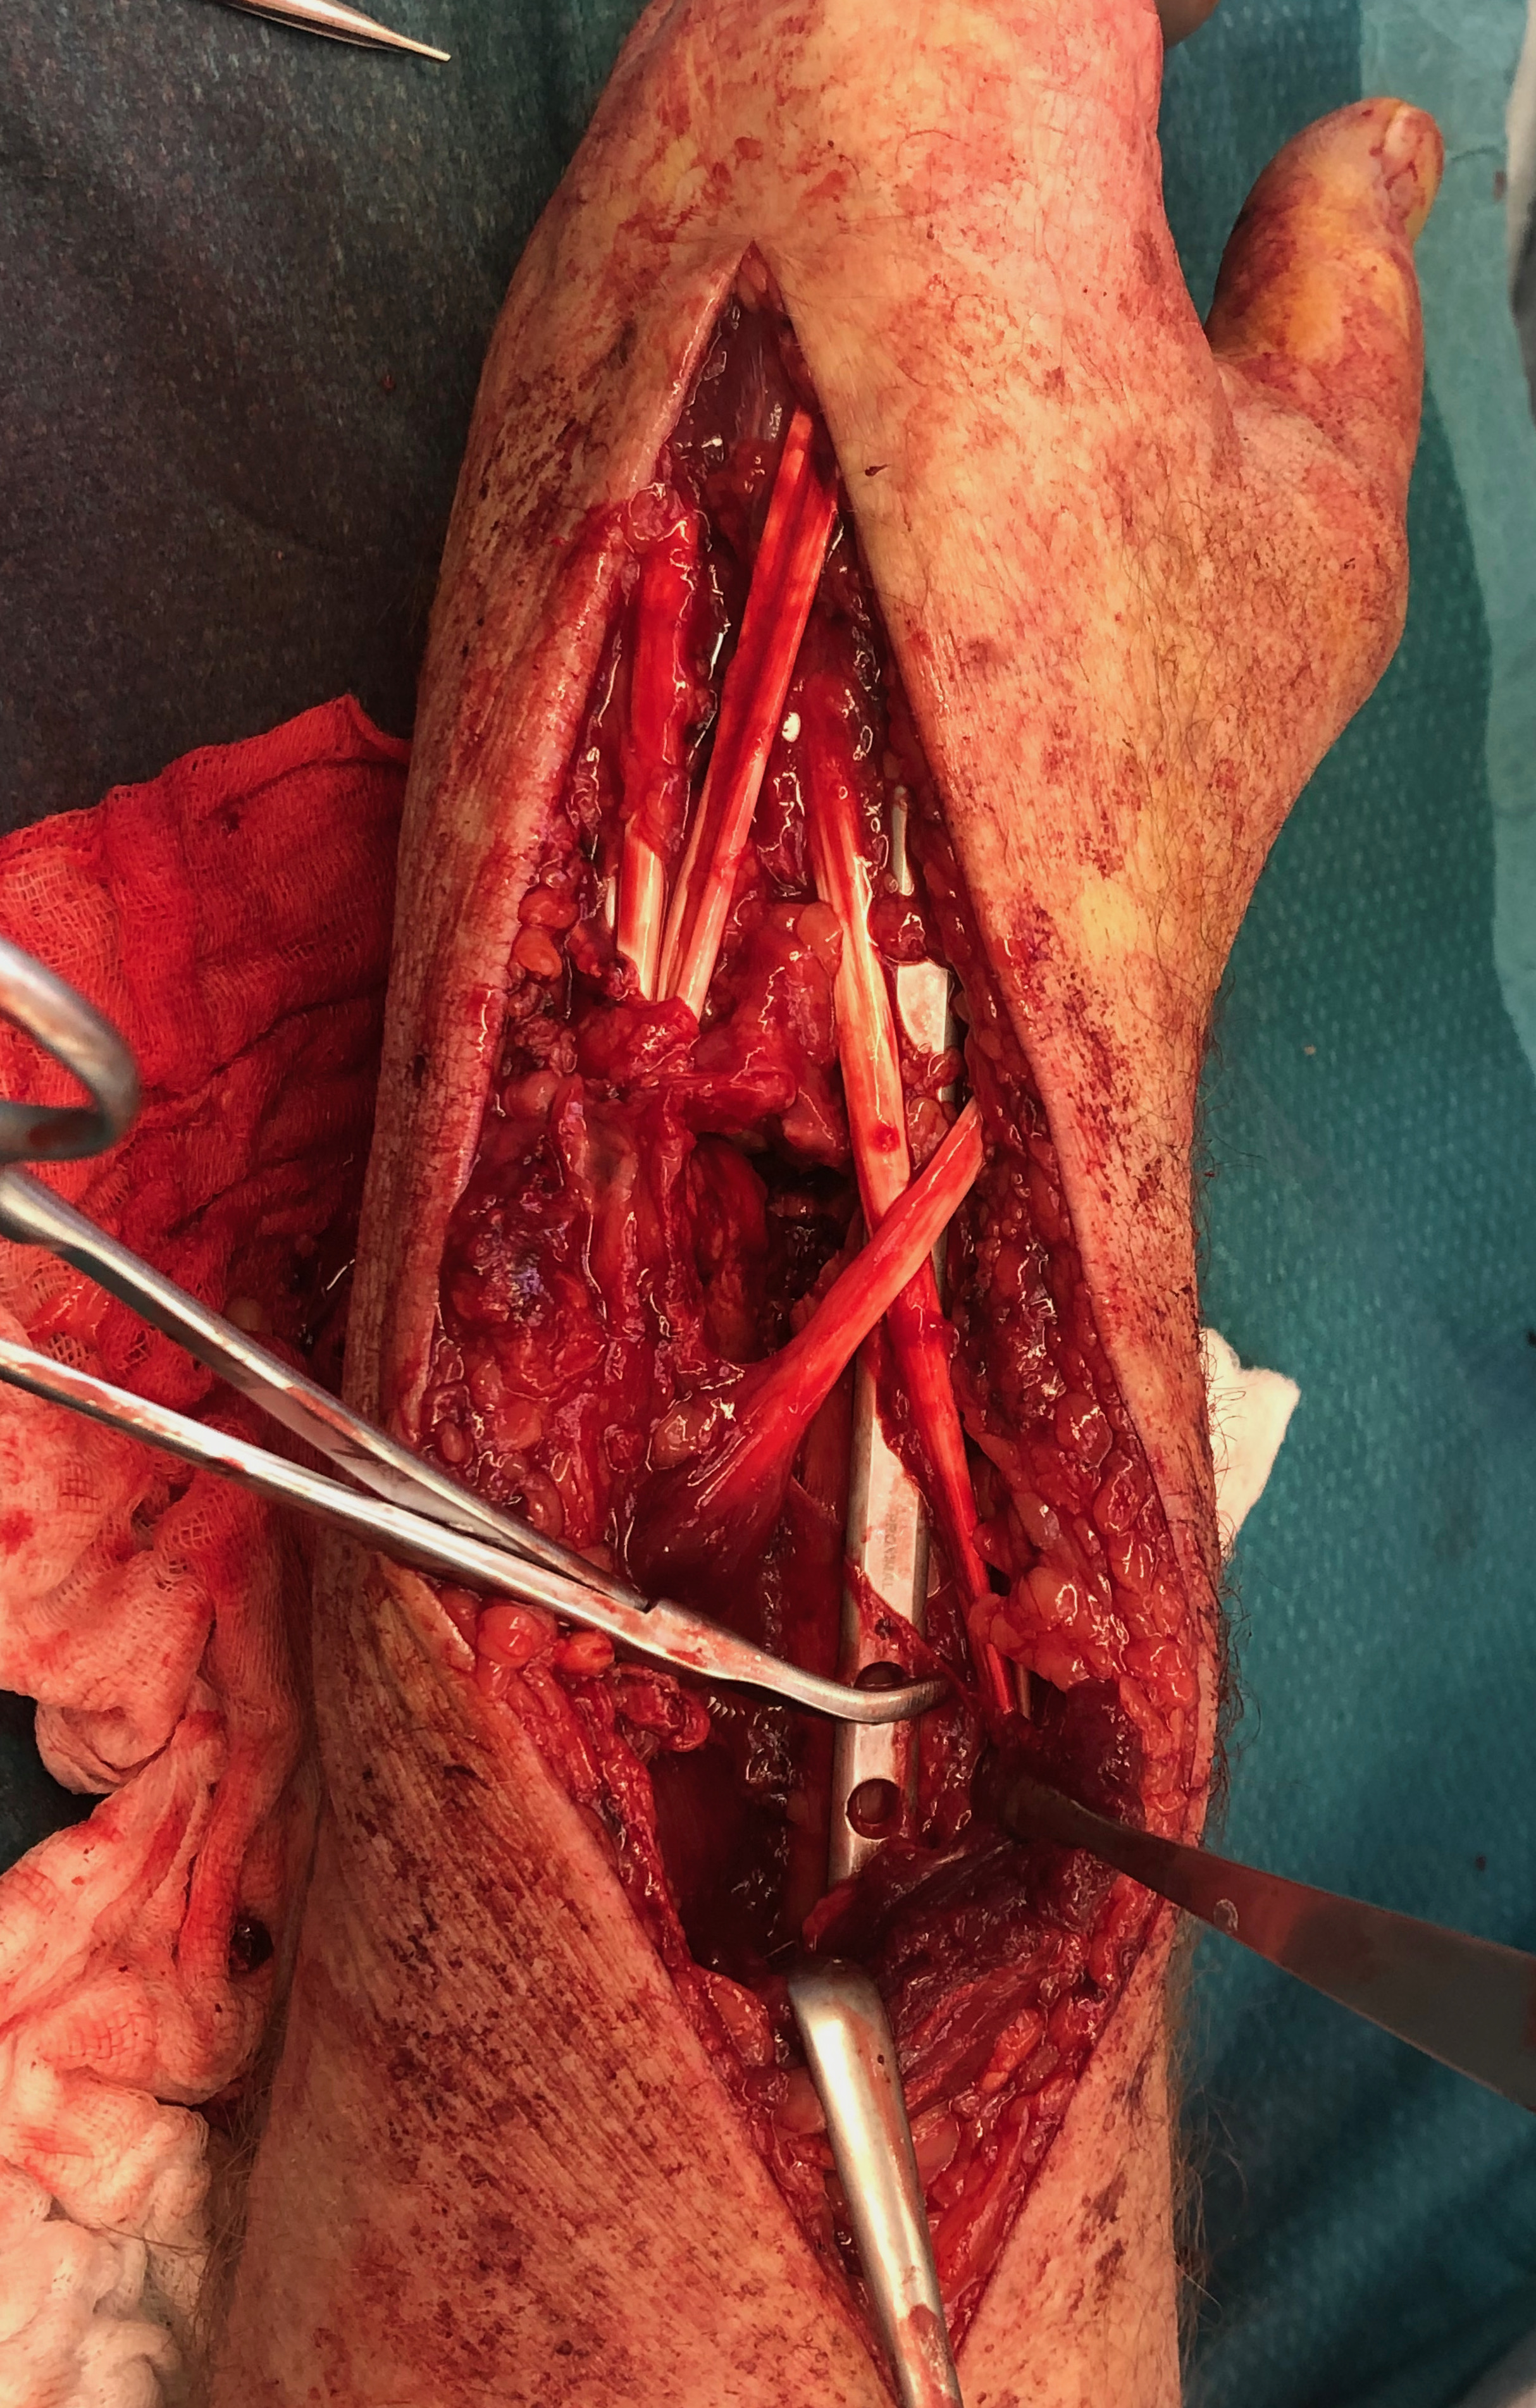

Dorsal distraction plating

Technique

Extended dorsal approach

- protect sensory radial nerve

- open 3rd extensor compartment / retract EPL radially

- mobilized 4th extensor compartment / retract EDC ulnarly

- bare area of radius proximally between EDC and ECRB / ECRL

Fixation to 2nd or 3rd metacarpal first

- 2nd metacarpal: under 2nd extensor compartment

- 3rd metacarpal: under 4th extensor compartment

- reduce / distract joint

- +/- additional radius fixation